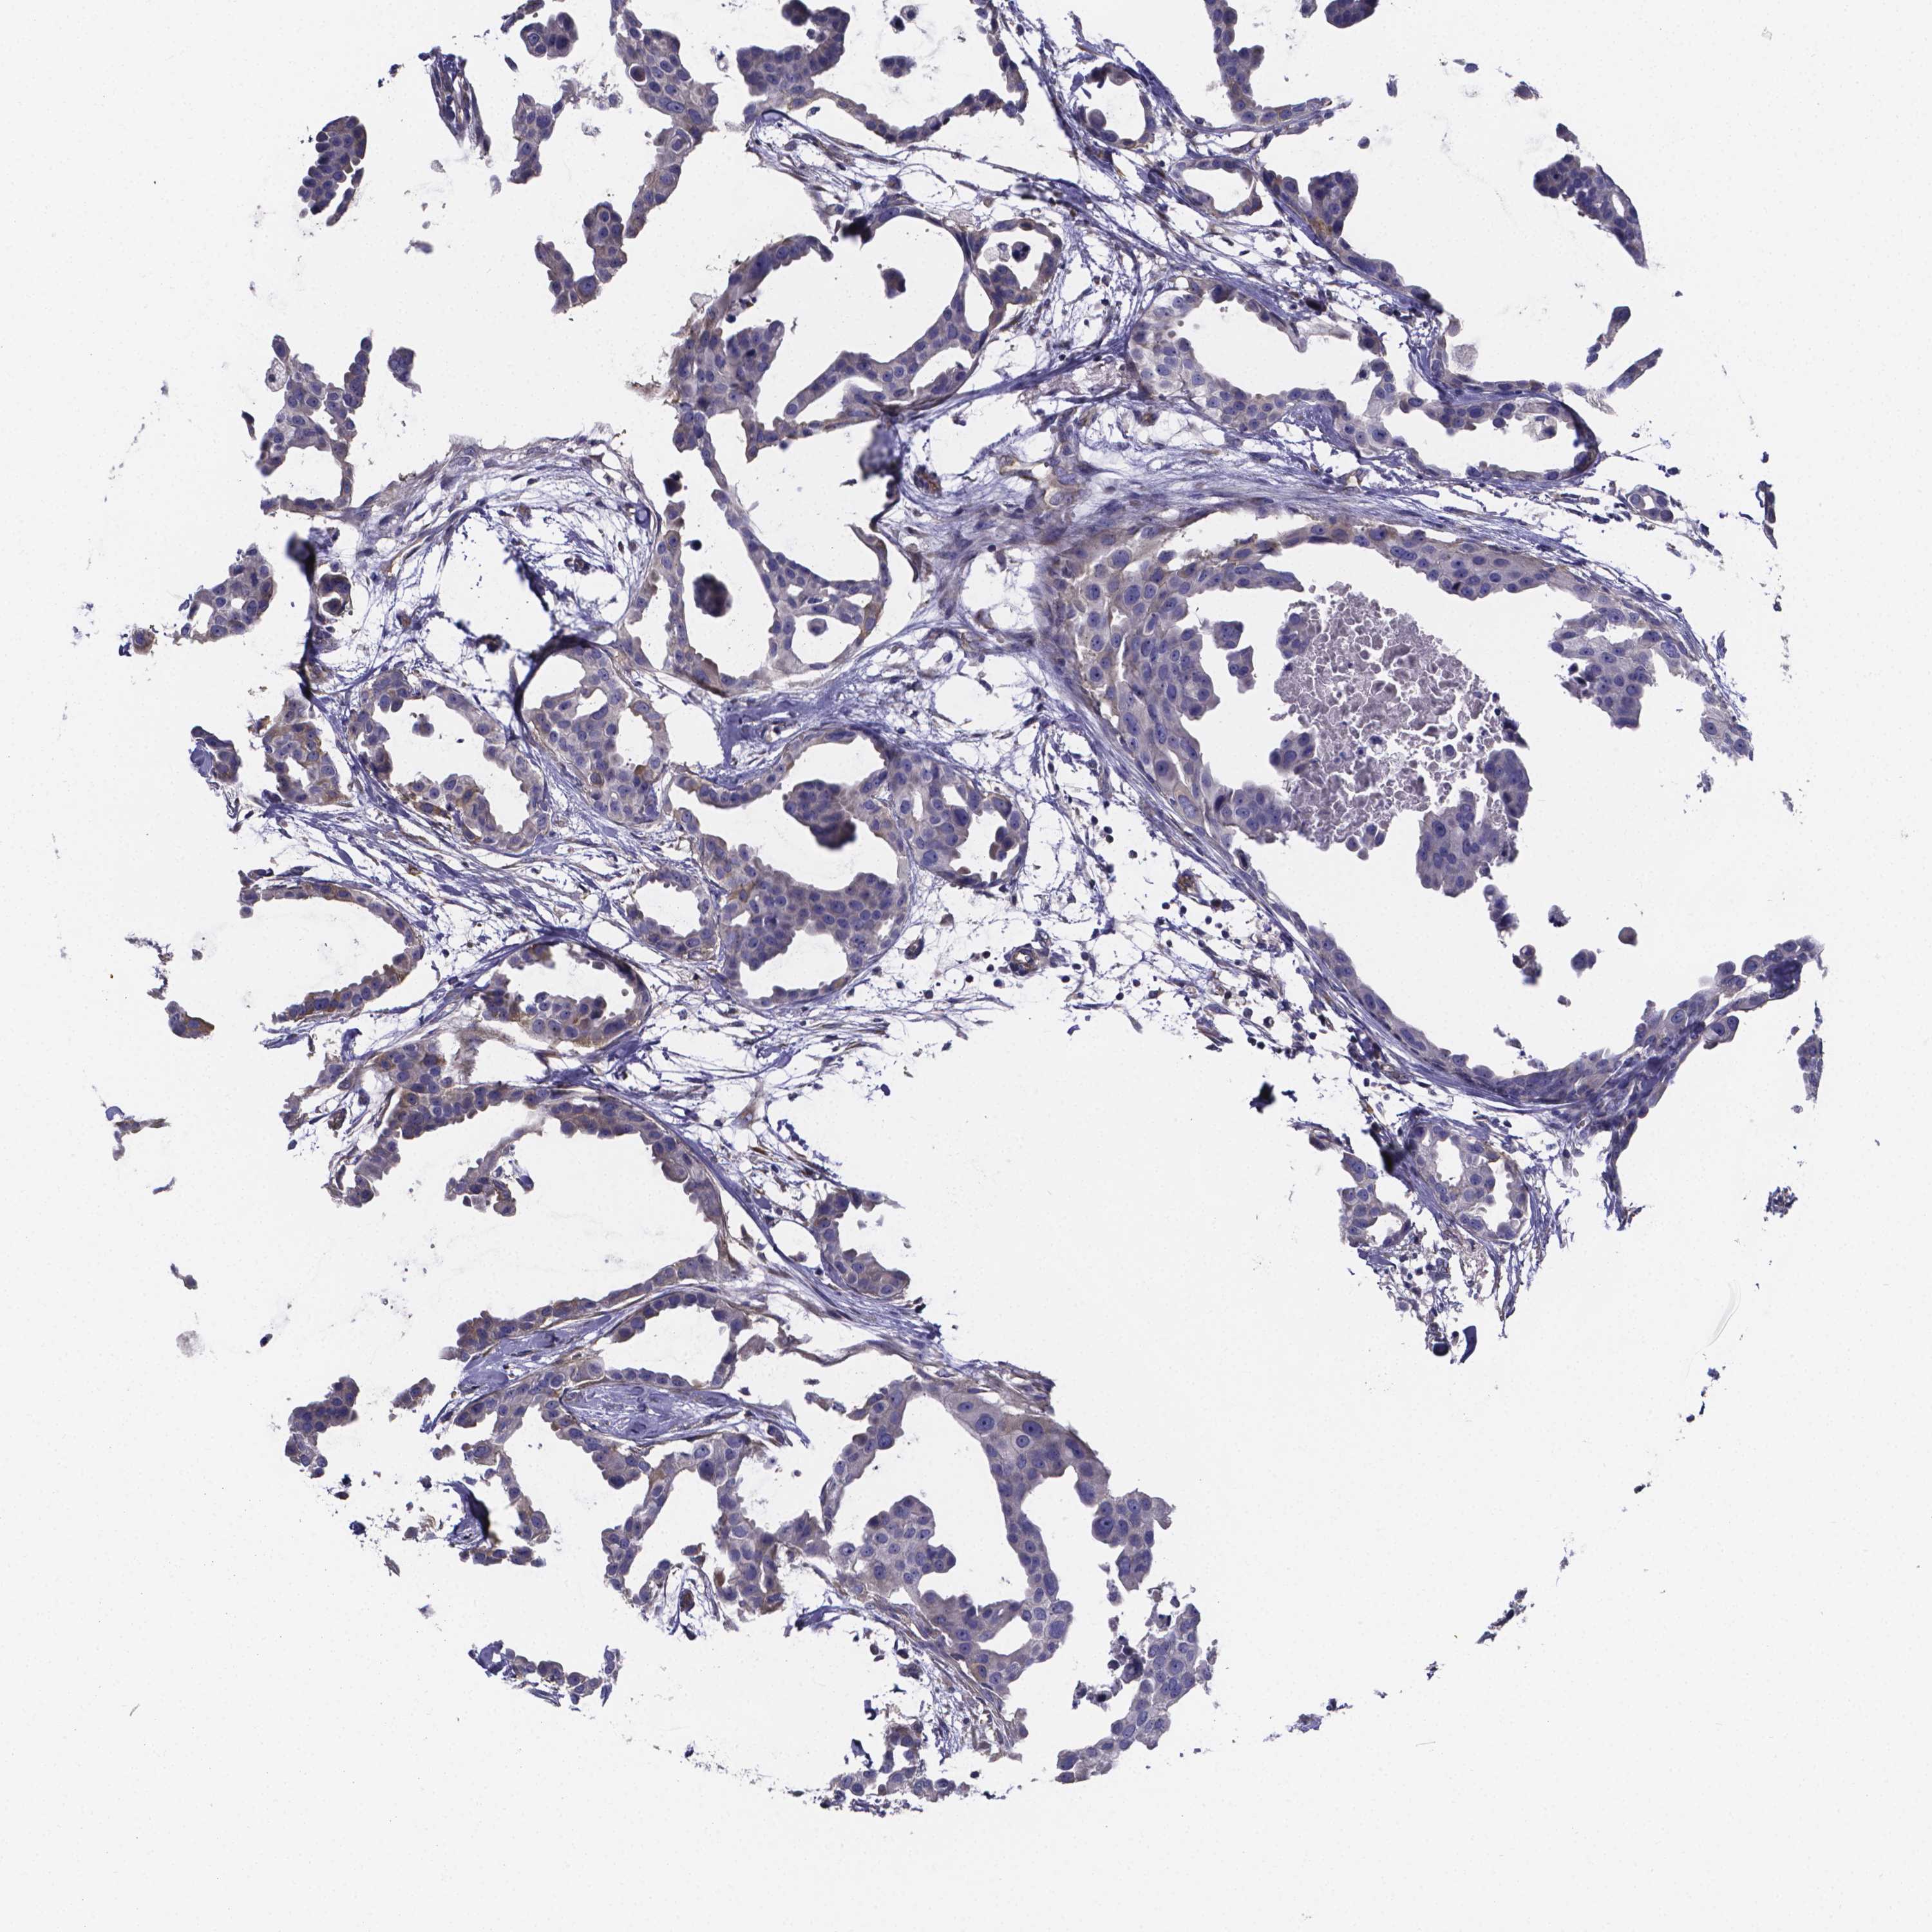

BRCA TCGA BRCA VALIDATION PROTEIN EXPRESSION

ANTIBODIES

AND

VALIDATION